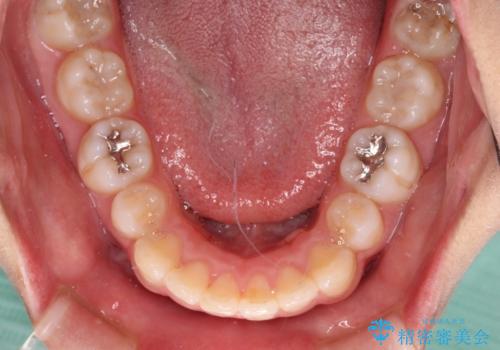

抜歯矯正の後戻り インビザライン・ライトによる矯正治療

治療途中、妊娠・出産があり、1年近く治療が停滞しましたが、無事に終了することができました。

インビザライン・ライトは提供されるマウスピースの数に制限があり、通常のタイプよりもマウスピース提供期間が短くなっている一方、安価に治療を行うことができるプランです。

治療のゴールも変更できないため、軽微な歯列不正や、後戻り改善などに適しています。